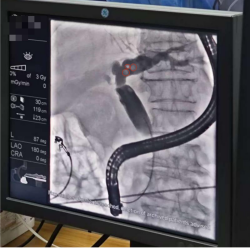

ERCP(内窥镜逆行性胰胆管造影)清晰显示胆总管结石

内镜清晰显示

胆总管内分布着多枚大小不等的褐色结石

整个手术过程在高清内镜直视下进行,医生操作精准,有效避免了对胰胆管黏膜的损伤。手术历时 30分钟,顺利完成。